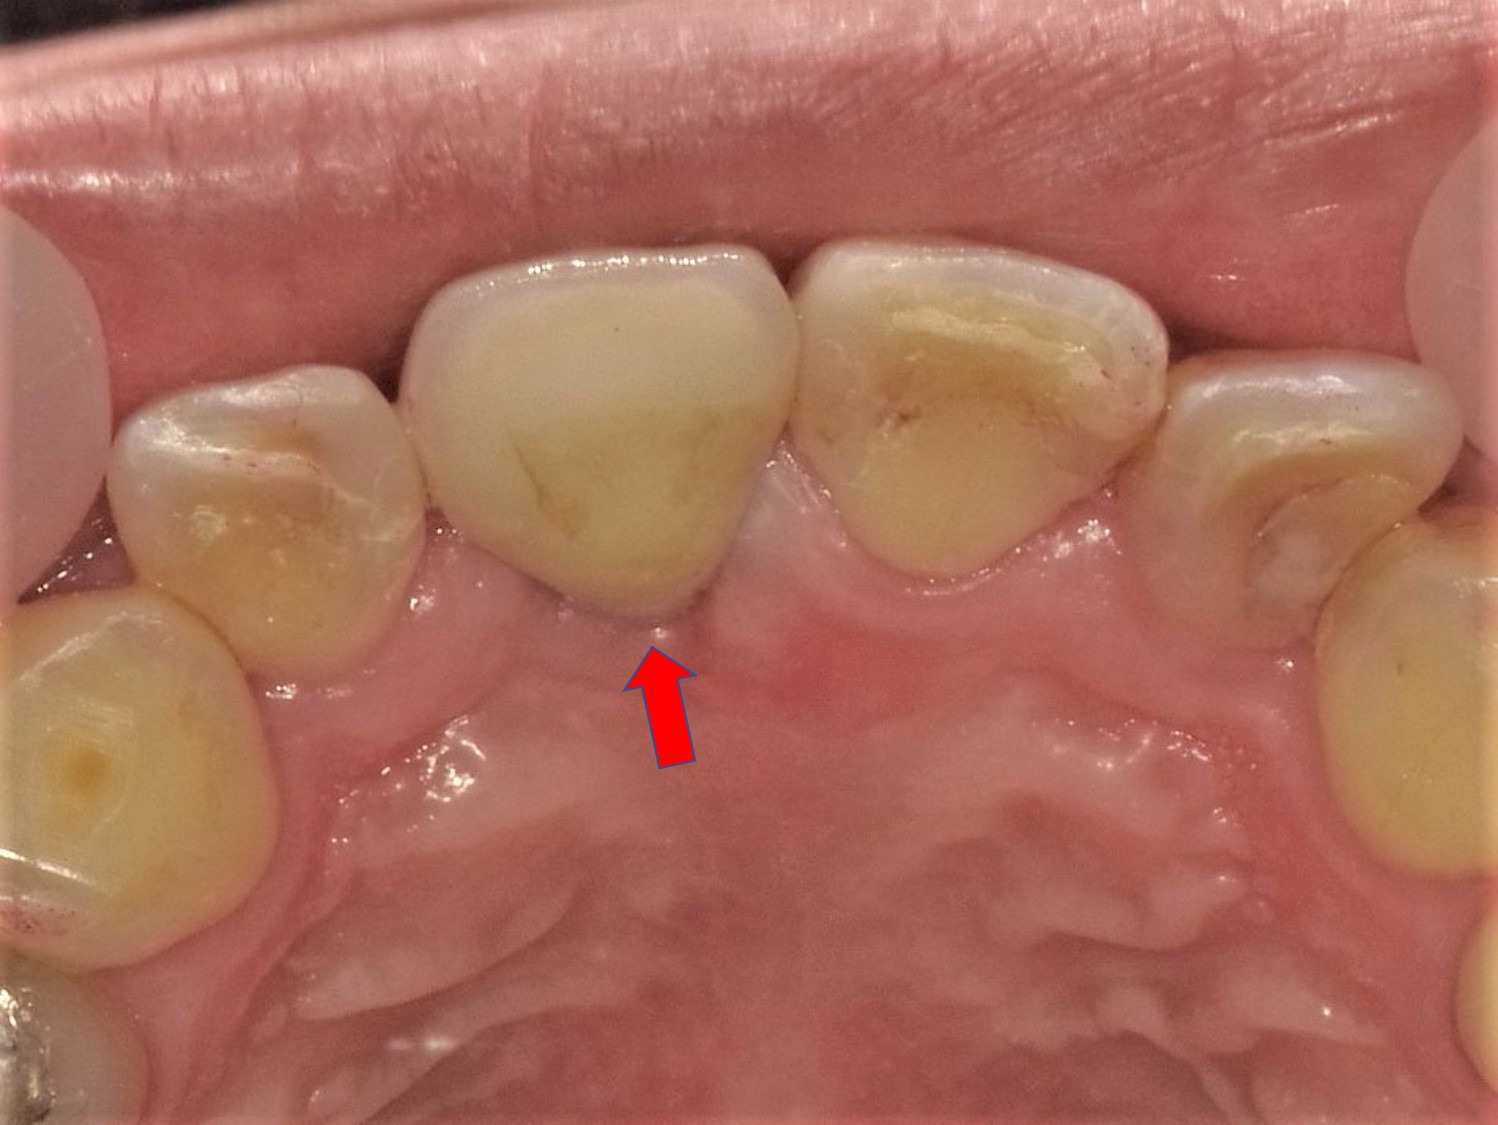

右側上顎中切歯の欠損症例(他院で骨造成が必要と診断され、当院の2倍以上の費用がかかると言われた)

(40歳代 男性)